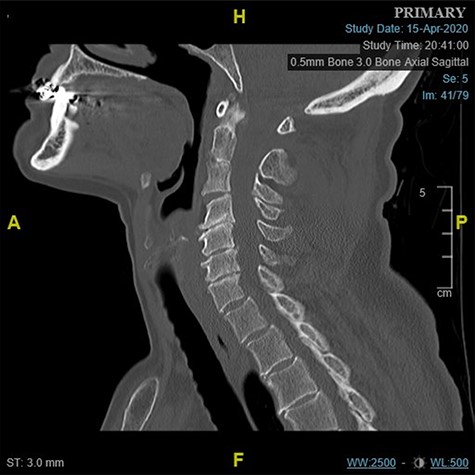

There is an acute fracture of the antero-superior osteophyte of the body of C7 (Fig. 2a). There is also opening of the cervical facet at C6/7 (Fig. 2b). There were no fractures of the vertebral bodies. It can also be appreciated that there is significant degenerative change between C4 and C7.

(a) Para-midline sagittal CT scan of the cervical spine at the time of first presentation showing a fracture of the antero-superior osteophyte of C7 (indicated with a circle). and (b) Para-midline sagittal CT scan of the cervical spine at the time of first presentation showing opening of the C6/C7 facet joint (indicated with a circle).